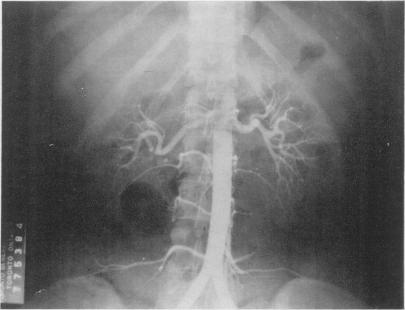

https://cdn.ncbi.nlm.nih.gov/pmc/blobs/2675/2249027/f999dc4d5a80/tacca00118-0169-a.jpg